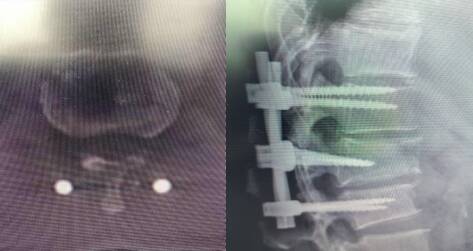

创伤骨科主任李光胜接到急诊会诊通知后,马上赶到急诊科会诊,检查发现病人血压80/50mmHg,心率110次/分,呼吸急促,胸廓挤压试验阳性,胸腰段压痛、叩痛明显,双下肢肌力3级,皮肤痛觉减退,肛门反射消失,肛门括约肌松弛,不能收缩,结合CT检查诊断为创伤失血性休克,腰1椎体爆裂骨折、椎管狭窄、合并双下肢截瘫、神经源性膀胱、神经源性直肠、尿潴留,L1、L2、5椎体骨折,L1棘突骨折、L1、3左侧腰椎横突骨折,左侧多发肋骨骨折、肺挫伤、双侧血气胸、头部外伤、左顶部头皮血肿。

手术顺利,历时3小时成功完成。术后CT、DR示骨折快复位,椎管无狭窄,椎体高度及序列恢复。由于患者为多发伤,围手术期管理同样至关重要。为此,骨外科医护团队制定详细快速康复方案,在内分泌科、普外泌尿科、康复医学科、中医科等多科室密切协作下,患者恢复顺利。